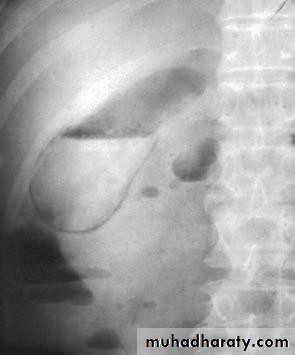

•  Plain radiogaph:

•  Radiopaque gall stones in 10%

•  Porcelain GB.. calcified GB..25% CA.

•  Limey bile

•  Gas in the wall, emphysematous cholecystitis

• Porcelain GB

• Gas in gall bladder